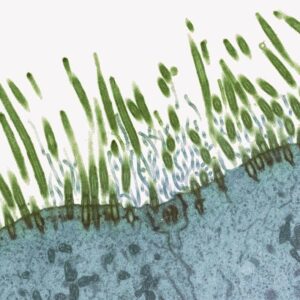

Transmission electron micrograph (tem) of a section of nasal lining.

Transmission electron micrograph (TEM) of a section of nasal lining through cilia (green) covering the epithelial lining of the nasopharyx, the part of the throat behind the nasal cavity. Cilia are microscopic hair-like structures that are covered with a sticky mucus, and trap dust and other inhaled particles. Co-ordinated wave-like beating of the cilia propels the mucus backwards towards the throat, where it is swallowed. Also seen are microvilli (blue), which increase the cell’s surface area. Magnification: x6000 when printed at 10 centimetres wide. Credit: Steve Gschmeissner/Getty Images

One of the many reasons we are told to breathe through our noses is that little hairs, known as ‘cilia’, filter out small particles and pathogens, shuffling them along the nasal passageways, down the throat and into the stomach – avoiding the lungs.